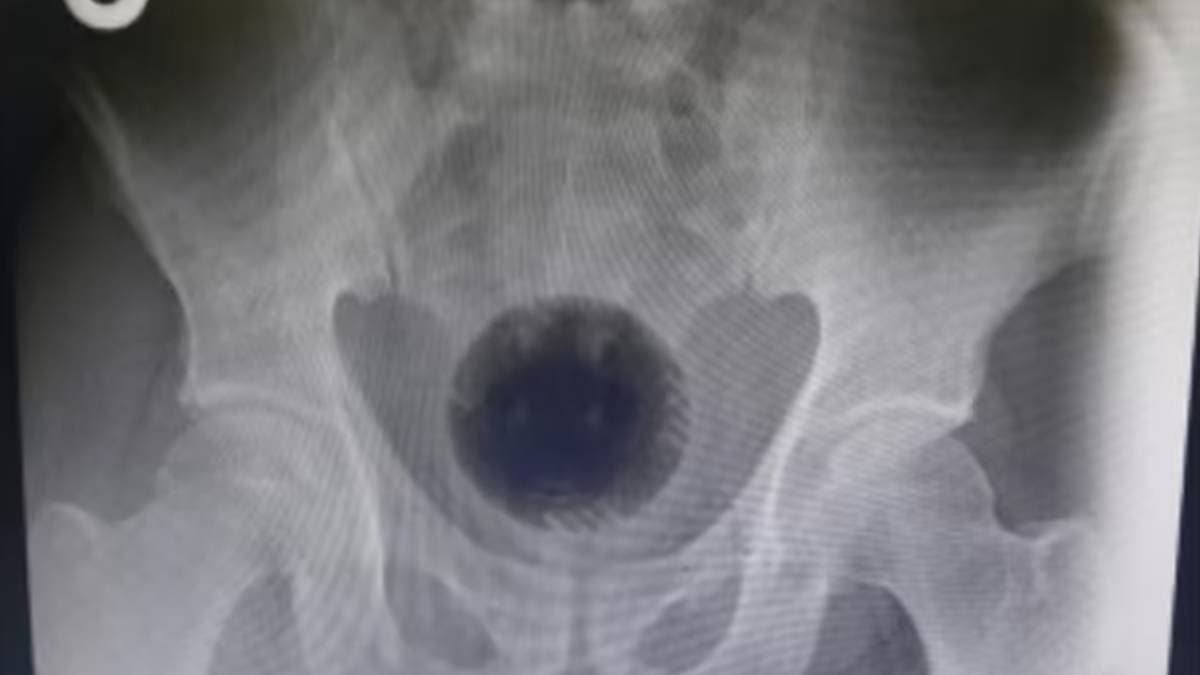

মৃত সাবেরের মেয়ে বর্তমানে মাধ্যমিক পরীক্ষার প্রস্তুতি নিচ্ছেন। মর্মান্তিক এই ঘটনায় পুরো পরিবার শোকাহত। মিল কর্তৃপক্ষ পুলিশের কাছে একটি সাধারণ ডায়েরি (জিডি) করেছে। চিকিৎসকরাও এই ঘটনায় স্তম্ভিত। তাঁরা জানান, এমন ধরনের রোগী খুবই বিরল, যেখানে মলদ্বারের মাধ্যমে জোর করে বাতাস ঢোকানো হয়েছে, ফলে পেটের নাড়িভুড়ি ফেটে গেছে।

ঘটনার পর সাবেরকে আশঙ্কাজনক অবস্থায় প্রথমে উলুবেড়িয়া ইএসআই হাসপাতালে নিয়ে যাওয়া হয়। পরে তাঁর অবস্থা আরও খারাপ হলে তাঁকে মানিকতলা ইএসআই হাসপাতালে পাঠানো হয়। চিকিৎসকরা তাঁকে ভেন্টিলেশনে রাখেন এবং বিভিন্ন আধুনিক চিকিৎসা পদ্ধতি প্রয়োগ করা হলেও, শেষ পর্যন্ত তাঁকে বাঁচানো যায়নি। মর্মান্তিক এই ঘটনায় স্থানীয় বাসিন্দাদের মধ্যেও শোকের ছায়া নেমে এসেছে।